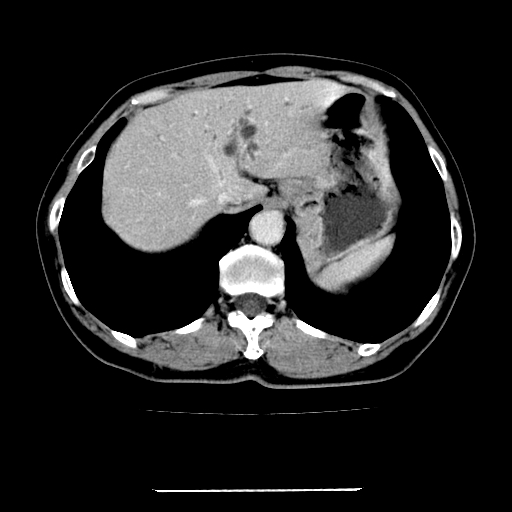

女,67岁,上腹部疼痛一周伴皮肤黄染,无发热。

左叶肝内胆管结石,并远端肝内胆管扩张。

肝内外胆管结石并肝内胆管扩张。

肝内外胆管扩张,左叶胆管内结石

考虑肝胆管癌;胰头占位?【形态失常,体积增大】

1、肝门高密度影下层面和胰头层面可见轻度胆管扩张,而静脉和延迟期均未见扫描完胰头,不能完全排除胰头占位。2、肝门部高密度影,考虑钙化或结石。